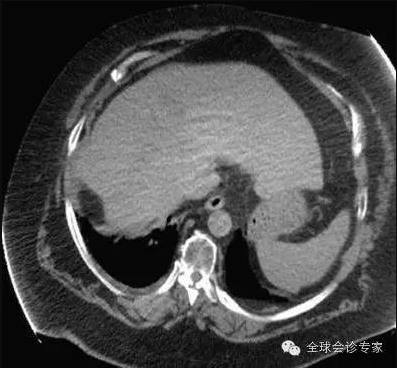

患者手术过程中无任何不适,每次治疗后正常回家。2015年5月回访,患者一般情况良好,体重明显增加。经影像检查,肝脏巨大肿瘤被彻底清除,脑部肿瘤几乎完全消除,且没有复发。生化检查,肝功能未见正常。

肝脏肿瘤治疗后彻底消失